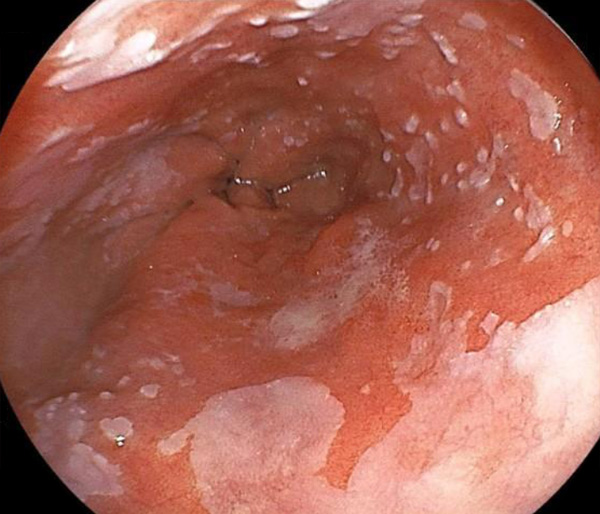

内視鏡所見と病理組織像の1対1対応が可能な症例を公募いたします。主にLSBEに発生した早期癌(HGDを含む)を対象としますが、興味深い症例であればSSBE癌でも結構です。採否は世話人へご一任ください。

特に、本邦では極めて稀なlong segment Barrett’s esophagus(LSBE)から発生した早期癌は、診断に難渋する場合も多く、欧米ではランダム生検による検出が標準的とされています。背景のBarrett食道もろとも全体を内視鏡切除+ラジオ波焼灼する欧米と異なり、ESDで内視鏡的な局所切除が基本の本邦では、存在診断+範囲診断(特に水平)を的確に行うことが不可欠です。

そのためには、一流の病理医による組織学的診断とエキスパート内視鏡医による拡大内視鏡像との一対一対応を徹底的に行うことで、『本来、見えないであろう拡大所見の先にある組織構築像が診えてくる』所まで内視鏡診断レベルを上げていく必要があります。その実現には、一対一対応を追究した症例(特にLSBE発生例)1例でも多く経験するしかありません。本研究会でBarrett食道腺癌(LSBE発生早期病変)を共に学び、拡大内視鏡像の一歩先を診るスキルを習得しましょう!一人でも多くの皆様のご参加をお待ちしています。

私は、Barrett食道癌はHGDも含め、内視鏡による存在診断、範囲診断が可能と信じて来ました。しかし最近、NBI拡大観察を併用しても側方範囲診断が不可能なLSBE症例を経験しました。診断技術を向上させるためには、多くの症例を診るしかありません。そこで、Barrett食道に造詣の深い先生方に世話人をお願いし、Barrett食道研究会を立ち上げることに致しました。全国からLSBE症例を集め、内視鏡的、組織学的診断に迫りたいと思います。皆様のご参加をお待ち致します。